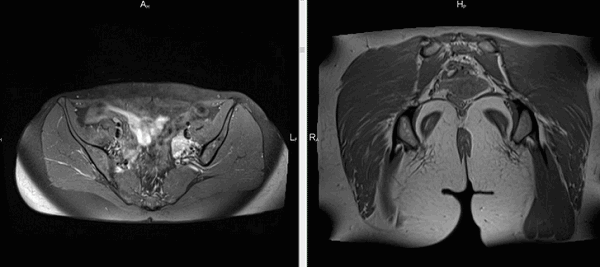

А - лимфаденопатия, В - зоб щитовидной железы

Магнитно-резонансная томография тазового пояса

Рыхлые структуры ягодичной области исследуют при возникновении:

выраженных болей в нижней части спины;

парестезии в зоне поясницы, крестца, ног;

застойных явлений, нарушений кровообращения в области малого таза и ягодиц.